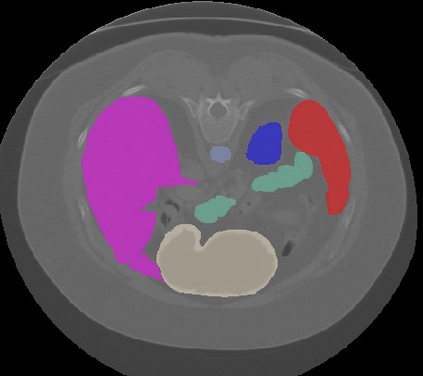

Transformers, the default model of choices in natural language processing, have drawn scant attention from the medical imaging community. Given the ability to exploit long-term dependencies, transformers are promising to help atypical convolutional neural networks (convnets) to overcome its inherent shortcomings of spatial inductive bias. However, most of recently proposed transformer-based segmentation approaches simply treated transformers as assisted modules to help encode global context into convolutional representations without investigating how to optimally combine self-attention (i.e., the core of transformers) with convolution. To address this issue, in this paper, we introduce nnFormer (i.e., Not-aNother transFormer), a powerful segmentation model with an interleaved architecture based on empirical combination of self-attention and convolution. In practice, nnFormer learns volumetric representations from 3D local volumes. Compared to the naive voxel-level self-attention implementation, such volume-based operations help to reduce the computational complexity by approximate 98% and 99.5% on Synapse and ACDC datasets, respectively. In comparison to prior-art network configurations, nnFormer achieves tremendous improvements over previous transformer-based methods on two commonly used datasets Synapse and ACDC. For instance, nnFormer outperforms Swin-UNet by over 7 percents on Synapse. Even when compared to nnUNet, currently the best performing fully-convolutional medical segmentation network, nnFormer still provides slightly better performance on Synapse and ACDC.